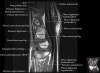

- Axial section

Axial T1 evaluates the tendons of the wrist and carpal tunnel, including the flexor retinaculum.